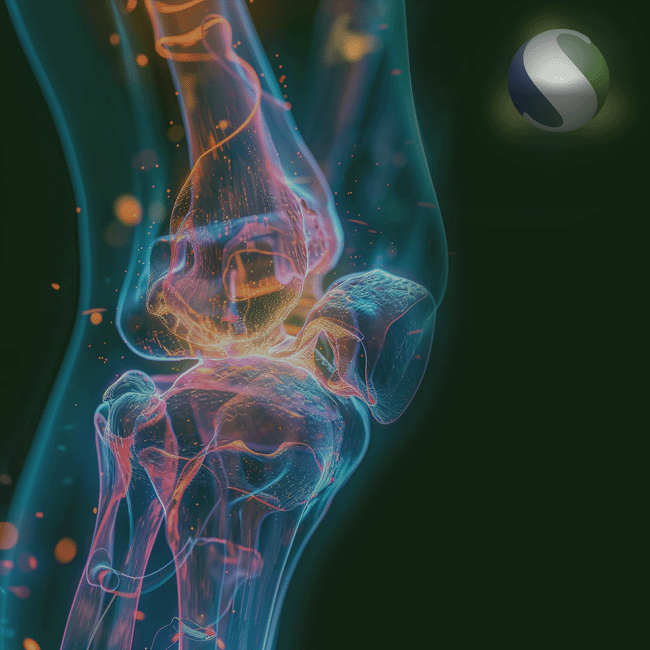

FIXADORES EXTERNOS

A linha de fixadores externos da Orthoset é projetada para oferecer versatilidade e segurança no tratamento de fraturas complexas, alongamentos ósseos e correções ortopédicas. Com sistemas modulares e de fácil aplicação, nossos produtos permitem o controle preciso da estabilidade e do alinhamento ósseo. Atuamos com marcas confiáveis que garantem performance clínica e suporte técnico, sempre com foco na reabilitação eficaz dos pacientes.

MEDICINA ESPORTIVA

Para atender às demandas da medicina esportiva, a Orthoset oferece soluções específicas voltadas à recuperação funcional, prevenção e tratamento de lesões musculoesqueléticas. Nossos produtos são pensados para atletas e pacientes com alta exigência física, promovendo retorno seguro à atividade com agilidade e desempenho. Trabalhamos com tecnologias modernas e eficientes, que atendem desde lesões ligamentares até intervenções ortopédicas mais complexas.